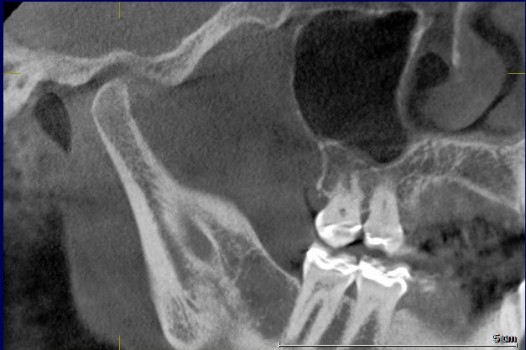

Over 40 million Americans suffer from Myofascial Pain Dysfunction (MPD), a condition that causes headaches and muscular pain. Dr. Klim uses advanced biofunctional diagnostic techniques to decrease painful tension in the head, neck, and shoulder muscles.

Many suffer from Myofascial Pain Dysfunction (MPD) and are not sure of the nature of their condition and how to solve it. You may have heard other terms that describe this condition such as TMJ or TMD. This is short for Temporomandibular Joints. Craniomandibular Dysfunction (CMD) or Temporomandibular Disorder (TMD) are another terms dentist use.